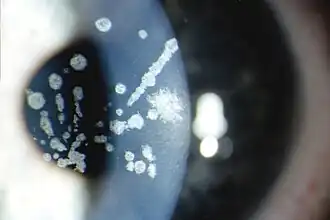

Opacidades en la córnea en la distrofia corneal de Avellino | ||

Los síntomas que provoca son depósitos en la capa de la córnea llamada estroma, por lo que esta pierde su transparencia, ocasionando perdida de visión. En muchas ocasiones el tratamiento recomendado es un trasplante de córnea, pero los depósitos pueden volver a producirse ocasionando de nuevo un deterioro de la visión.